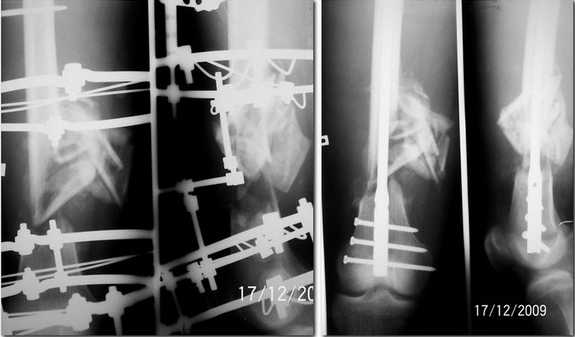

Re: застарелый открытый многооскольчатый перелом бедренной кости

Прислушавшись к мнению уважаемых коллег провели двухэтапное лечение пациента. Пару дней

назад забили штифт, без укорочения, колено редрессировали до 90гр. Всем спасибо за дельные

советы.

Уважаемые коллеги! Очень демонстративный и профессионально проведенный остеосинтез. Удачи, так держать! С уважением Ерсин Жунусов.